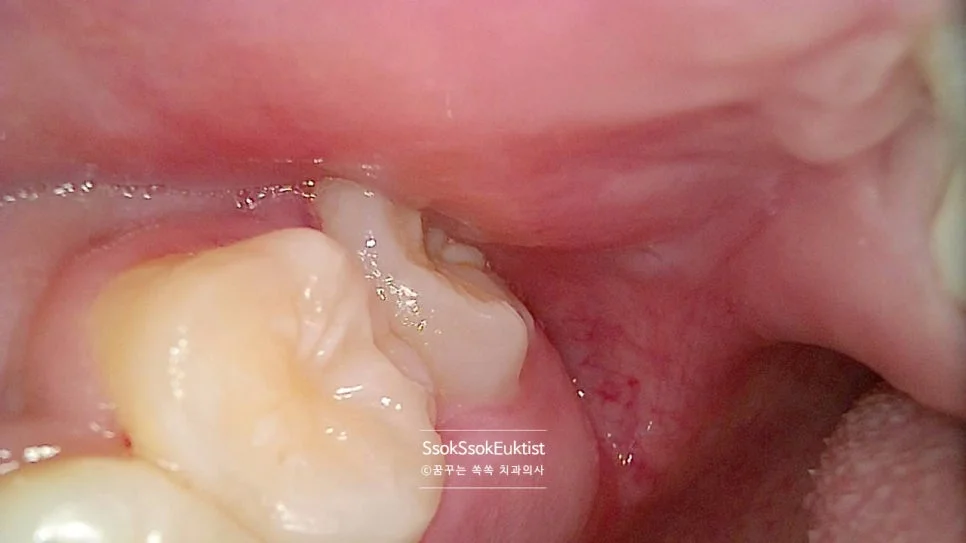

왼쪽 아래 사랑니가 앞 치아에 걸리지 않고 잘 올라왔는데 그만 뒤쪽에 턱뼈에 걸려버렸네요. 이런 경우 사랑니가 턱뼈의 잇몸에 의해 덮여있게 되고 만성적인 염증 상태가 되게 마련입니다.

이 또한 뒤쪽에 턱뼈에 걸리지 않게 길만 만들어주면 쉽게 발치할 수 있는 치아입니다.